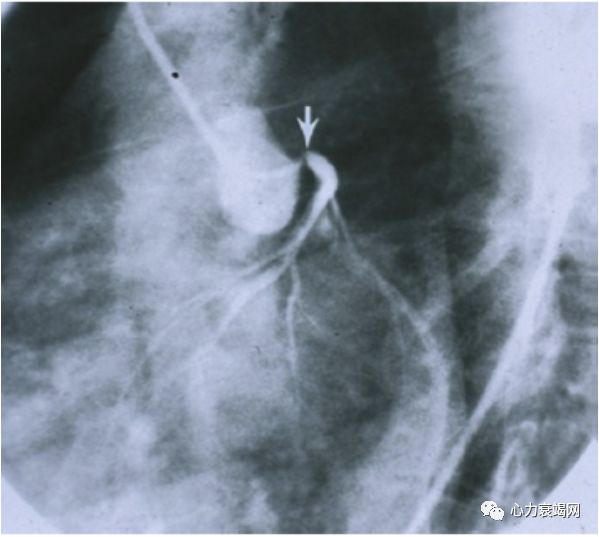

BP:(左上肢)161/114mmHg,(右上肢)140/?mmHg,下肢血压测不出

右侧肱动脉近心段局限性重度狭窄,

双侧股总、股浅动脉狭窄